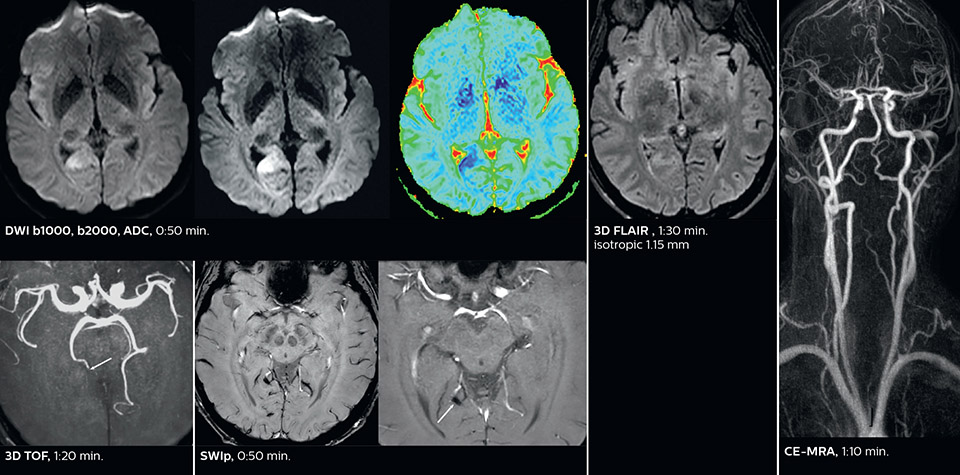

Dr. Savatovsky appreciates the improvements and flexibility that Elition with Compressed SENSE and MultiBand SENSE provides, particularly for stroke patients. “For stroke, it allows us to cut about 5 minutes off of our stroke protocol, or to keep the same acquisition time and get more insights.” The ability to perform more sequences can help in making a swift and confident diagnosis. “For example, our stroke cases usually include the regular sequences that every center does (b1000 diffusion, FLAIR, time-of-flight angiography), but we also image supra aortic vessels, and we can replace a gradient echo sequence with a fast 50-second susceptibility-weighted sequence, and all of this doesn’t add much time. because all the regular sequences are accelerated on Elition.” “The time savings with Compressed SENSE and MultiBand SENSE make it easier to add sequences to give us additional insights. Depending on the context and the first results, we might add a DSC perfusion to assess the ischemic penumbra, an ASL perfusion to help find an alternative cause in case of normal diffusion, or add a high-resolution T1 sequence for a stroke patient, to quickly assess wall imaging in emergency cases. The additional sequences can help improve patient management, because we can already consider some alternative diagnoses if the morphological MRI is normal.”

This is an example of acute ischemic stroke with distal occlusion of the right posterior cerebral artery. Note the improved visibility of the ischemic territory on the diffusion weighted image with high b-value. The 3D FLAIR shows a distal PCA occlusion. The fast SWIp depicts the thrombus on the isolated second echo image. The total scan time (including SmartBrain, preparations and a fast 3D T1w TSE Gd) is 8:00 minutes.

In this patient with acute right motor deficit and aphasia, the b2000 diffusion weighted image is normal. The SWIp image demonstrates more prominent veins in the right hemisphere, which could reflect increased deoxyhemoglobin contents. Fast ASL shows low CBF regions in the left frontal lobe. A follow-up ASL after one hour demonstrates high CBF values in the same area. The final diagnosis was migraine with aura.